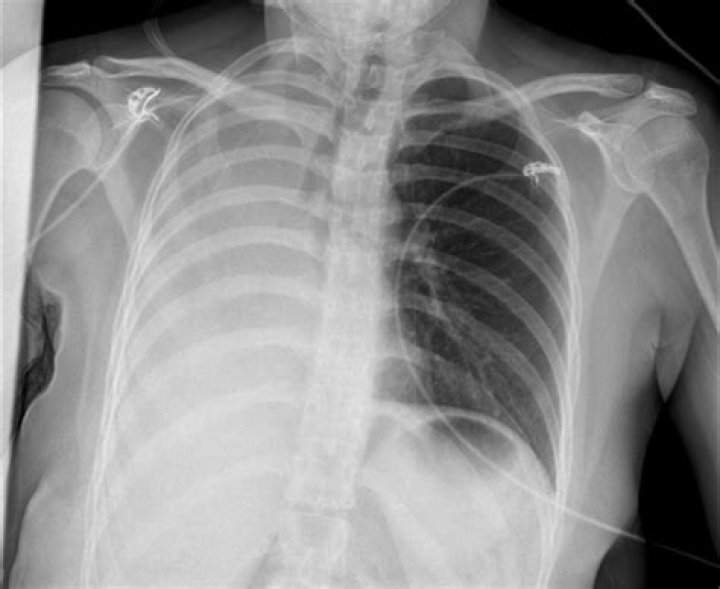

What happens when one lung collapses?

A collapsed lung occurs when air escapes from the lung. The air then fills the space outside of the lung between the lung and chest wall. This buildup of air puts pressure on the lung, so it cannot expand as much as it normally does when you take a breath. The medical name of this condition is pneumothorax.

Pneumothorax is the most common complication of transthoracic lung biopsy (4). A patient with stable pneumothorax may be treated conservatively without chest tube insertion. If pneumothorax is large (greater than 30% of hemithorax), is rapidly expanding, or is causing symptoms, chest tube insertion is warranted.

Pneumothorax. The most common complication of chest biopsy is development of a pneumothorax. The largest retrospective series placed the incidence of pneumothorax at 20.5% and the incidence of pneumothorax requiring chest drainage at 3.1%.